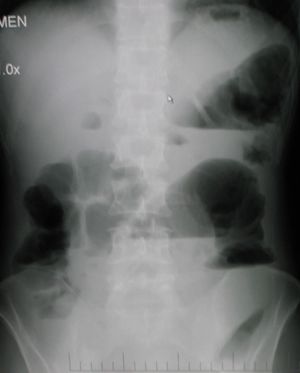

يوضح التصوير بأشعة إكس على البطن لمريض مصاب بانسداد الأمعاء الغليظة وهو في وضع الوقوف مستويات متعددة من السوائل والغازات وأجزاء منتفخة من الأمعاء.

من ضمن الأشياء التي يكشف عنها التصوير الإشعاعي وجود انتفاخ بالأمعاء ووجود مستويات متعددة (أكثر من ستة مستويات) من السوائل والغازات في صور الأشعة التي تؤخذ على البطن والمريض في وضع الاستلقاء على الظهر تارة والوقوف تارة أخرى.